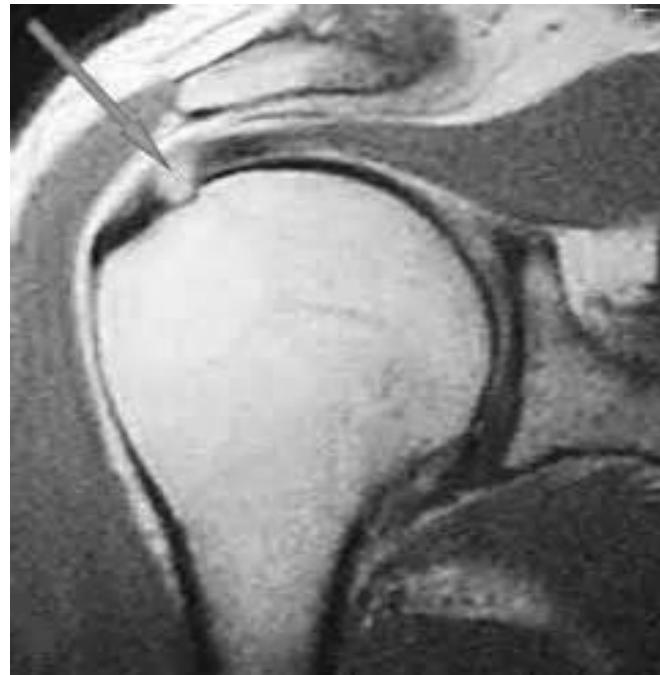

This patient has chronic shoulder pain (OA glenohumeral / subacromial pathology) has not responded to NSAIDs. You are required to inject the site with steroid and local anesthetic agent.

| For Glenohumeral joint: | |

o Feel the coracoid, go lateral to it from anterior![]() ![]() Posterior glenohumeral injection | |